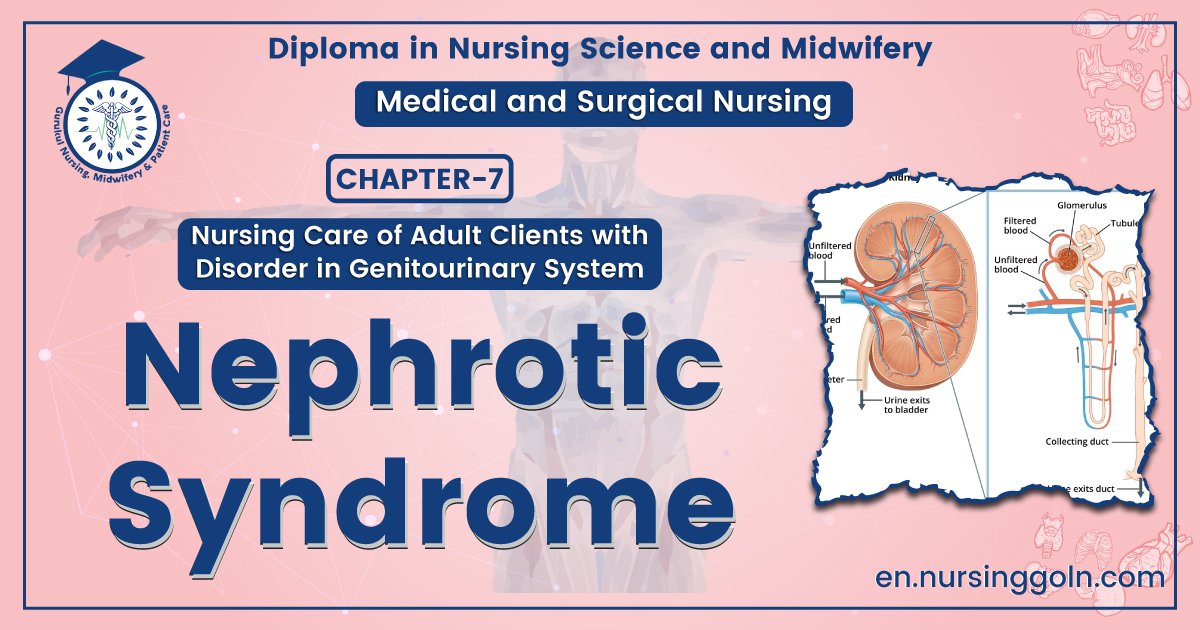

Definition of Nephrotic Syndrome:

It is clinical condition characterized by –

- Massive proteinuria (>3.5 gm/day)

- Hypo albuminaemia (<30 gm/L)

- Generalized oedema and

- Hypercholesterolemia

Nephrotic syndrome is a symptoms complex characterized by massive proteinuria, hypo albuminaemia, generalized oedema, hyperlipidemia and lipiduria.

Nephrotic syndrome is an alteration of kidney function caused by increased glomerular basement membrane permeability to plasma protein (albumin).